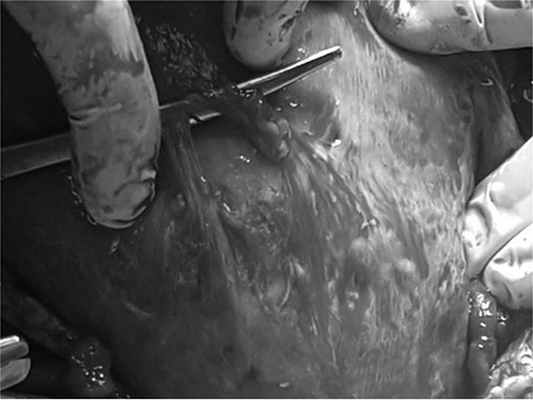

Операцию проводили под спиноэпидуральной анестезией. В целях создания более щадящих условий для плода, а также оптимального доступа к атипично расположенным узлам миомы применяли нижнесрединную лапаротомию; при этом матку достаточно осторожно выводили в рану. Полагаем также возможным проведение поперечного надлобкового разреза передней брюшной стенки при низкорасположенных узлах. При визуальном осмотре миоматозных узлов отмечался их отек, дистрофические изменения, у 27,9% (n=17) имелись кровоизлияния под капсулу опухоли; а у 14,7% (n=9) — частичный перекрут ножки опухоли. Зашивание осуществили отдельными викриловыми швами. В последующем этим беременным выполняли кесарево сечение, и рубцы на матке были полноценными (рис. 2, 3).

Рис. 2. Удаление миоматозного узла больших размеров с позадишеечным ростом. Фото.

Рис. 3. Состояние рубца на матке во время кесарева сечения после миомэктомии. Фото.